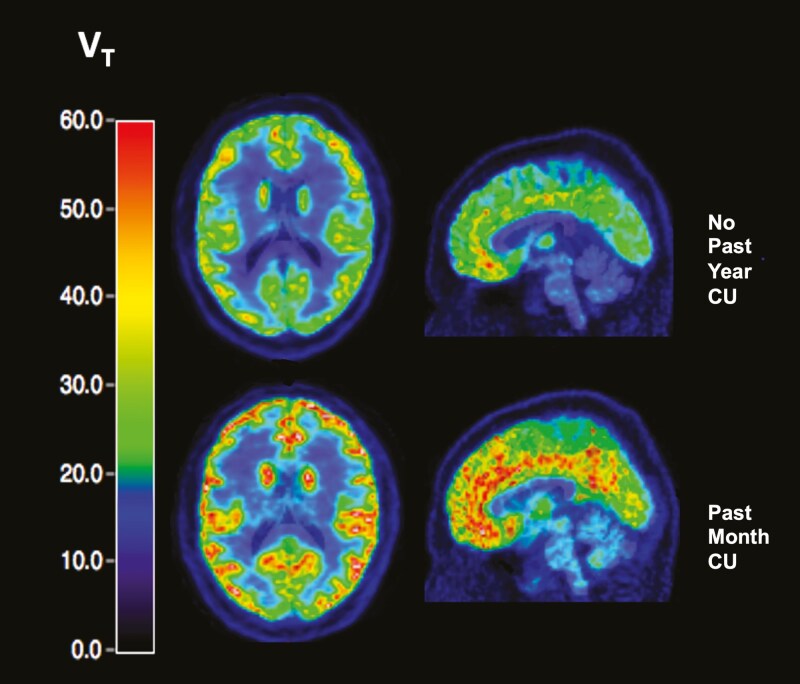

Methods: Using positron emission tomography with [18F]FPEB, we examined relationships between CU status and mGlu5 availability in vivo in a cross-diagnostic sample of individuals with trauma-related psychopathology (n = 55). Specifically, we tested whether mGlu5 availability in frontolimbic regions of interest (ROIs; dorsolateral prefrontal cortex, orbitofrontal cortex, ventromedial prefrontal cortex, amygdala, hippocampus) differed as a function of CU status.

Results: Past-year CU (n = 22) was associated with 18.62%-19.12% higher mGlu5 availability in frontal and 14.24%-16.55% higher mGlu5 in limbic ROIs relative to participants with no recent CU. Similarly, past-month or monthly CU (n = 16) was associated with higher mGlu5 availability in frontal (18.05%-20.62%) and limbic (15.53%-16.83%) ROIs. mGlu5 availability in the orbitofrontal cortex and amygdala was negatively associated with depressive symptoms in the past-year CU group. In both CU groups, exploratory analyses showed negative correlations between mGlu5 availability and sadness across all ROIs and with perceptions of worthlessness and past failures (r's = -.47 to .66, P's = .006-.033) in the ventromedial prefrontal cortex. Participants with CU reported lower mean depressive symptoms (P's = .006-.037) relative to those without CU.